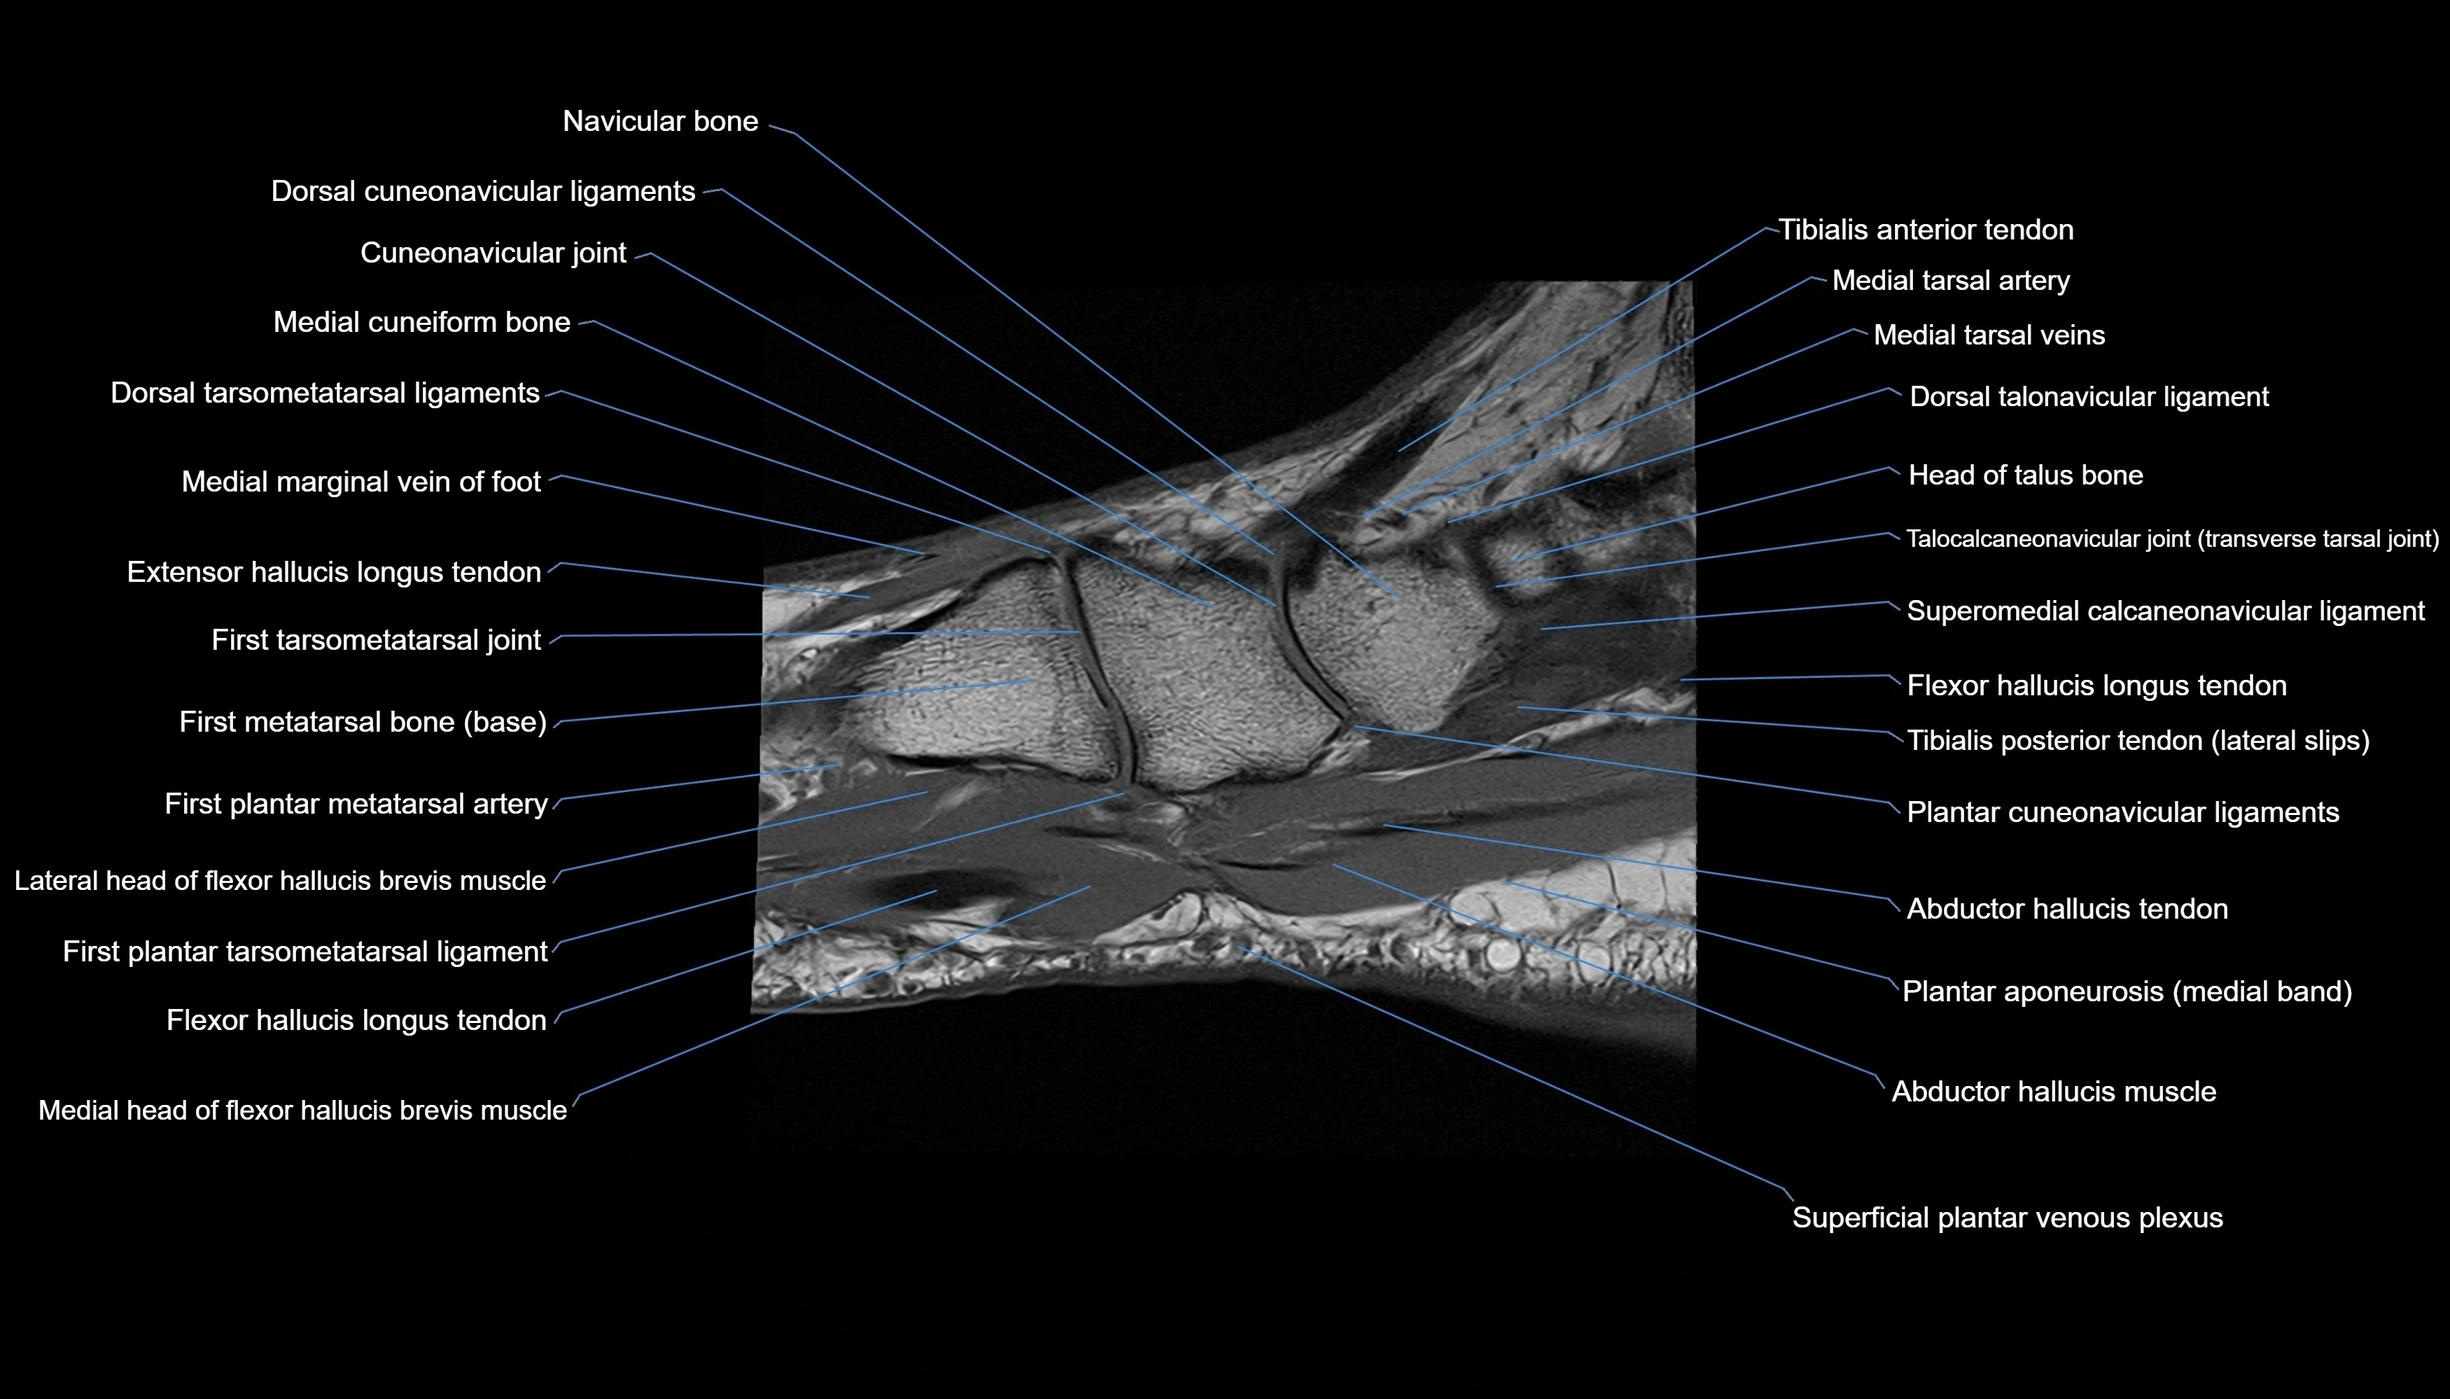

MRI image